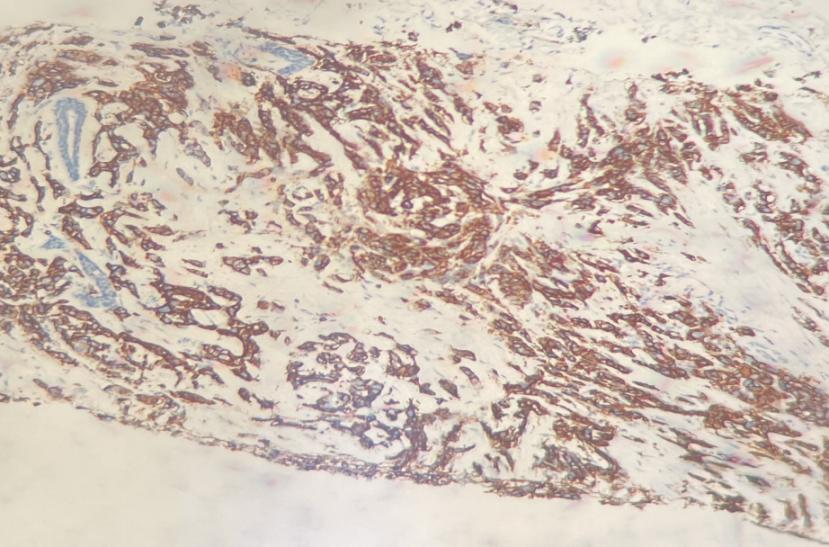

2021年11月3日右乳结节穿刺免疫组化:ER(-,0%),PR(-,0%),HER2(3+),Ki67(+45%)。

图1 HER2免疫组化